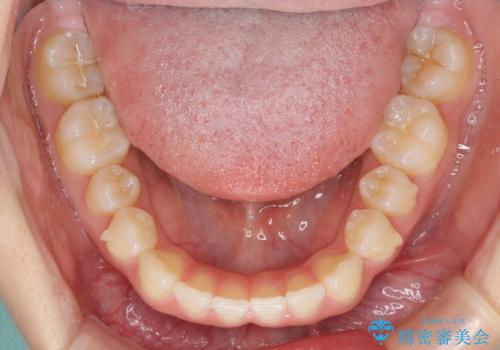

- 上の前歯の隙間を気にして来院された患者様です。

インビザラインにより、隙間を閉じながら、隙間の原因であるディープバイトを改善していくこととしました。

下顎の歯列が強く上顎に咬みこむことで隙間ができてしまうため、マウスピースの保定装置では後戻りのリスクが高くなってしまいます。

そのため、上下ともに前歯の裏側を細いワイヤーで固定し、その上から保定装置のマウスピースを使用していただくこととしました。